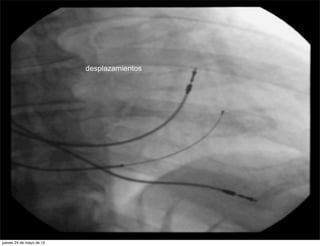

desplazamientos

COMPLICACIONES